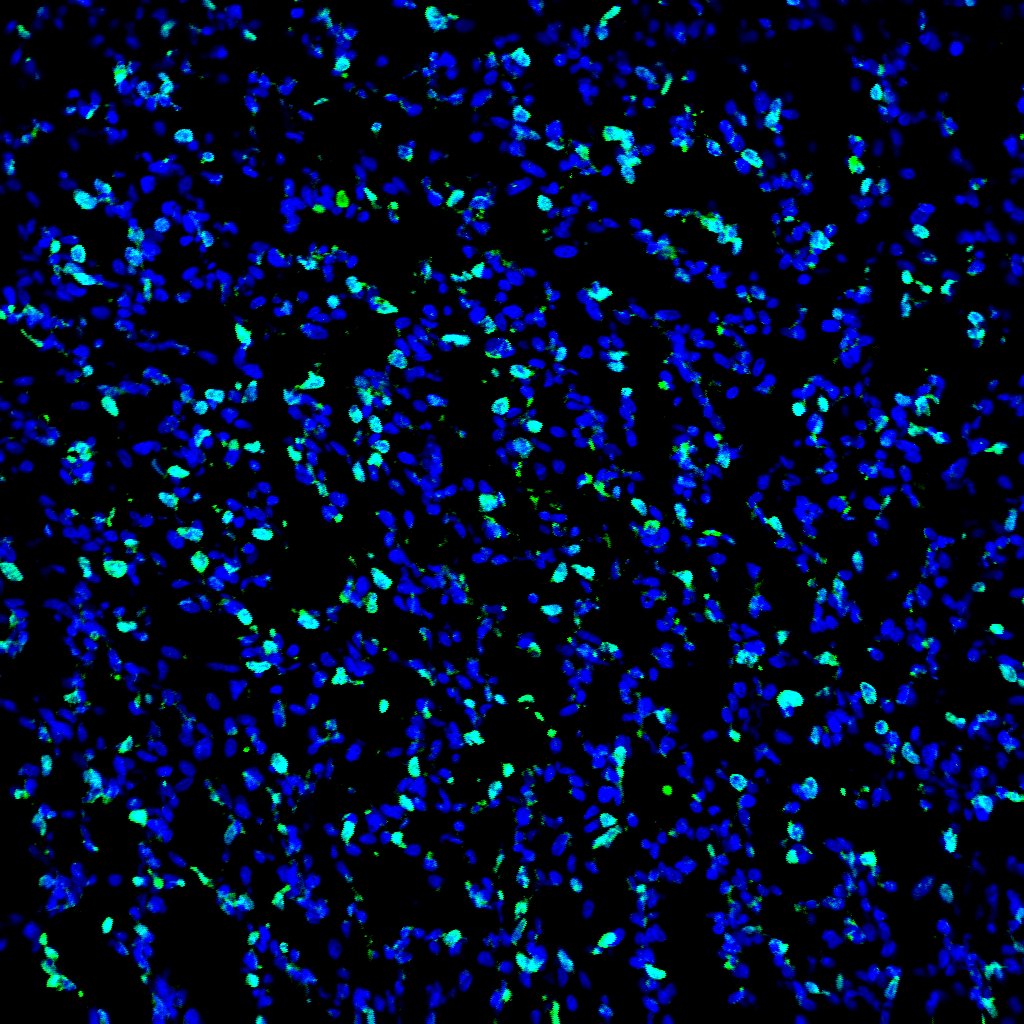

View Larger

Bromodeoxyuridine/BrdU in MCF‑7 Human Cell Line. Bromodeoxyuridine/BrdU was detected in immersion fixed MCF-7 human breast cancer cell line stimulated with BrdU using Mouse Anti-Bromodeoxyuridine/ BrdU Antigen Affinity-purified Monoclonal Antibody (Catalog # MAB7225) at 10 µg/mL for 3 hours at room temperature. Cells were stained using the NorthernLights™ 557-conjugated Anti-Mouse IgG Secondary Antibody (red; Catalog # NL007) and counterstained with DAPI (blue). Specific staining was localized to nuclei. View our protocol for Fluorescent ICC Staining of Cells on Coverslips.